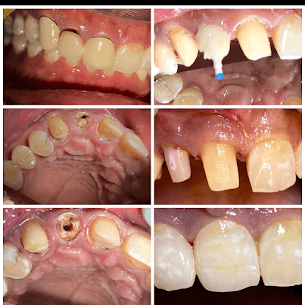

Periodontal Crown Treatment

- INFO:

Combined flap surgery and crowns for 62-year-old with gum disease